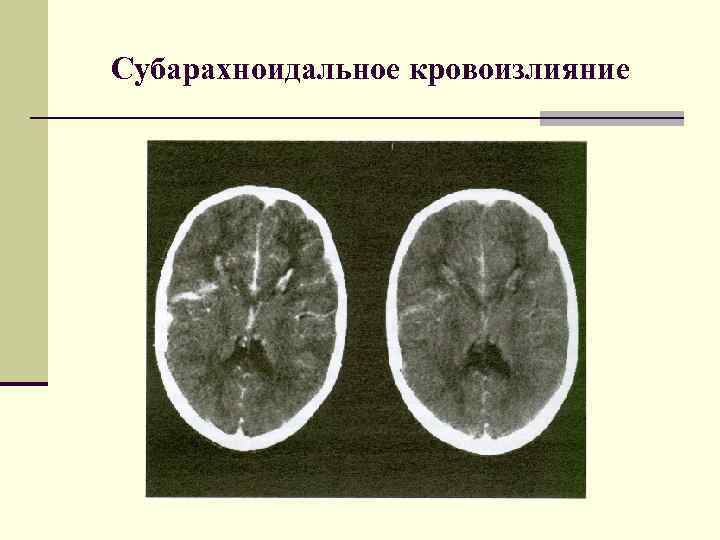

Субарахноидальное кровоизлияние Субарахноидальное кровоизлияние